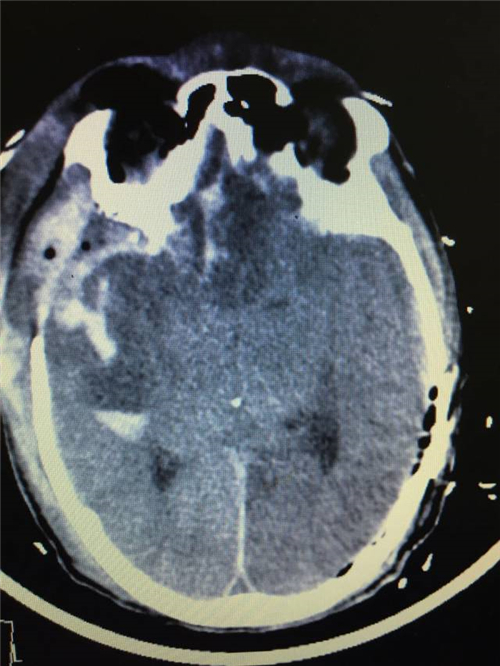

从患者到达我院再到开始手术仅仅花费40分钟,这为患者的进一步救治赢得了宝贵的时间。紧接着由我带领几名神经外科骨干,经过近2小时的手术,成功清除了患者颅内血肿。但此时患者肺部呼吸功能严重障碍,我们考虑患者颅底骨折发生误吸,导致气道不畅,立即请ICU会诊,ICU赵阳医生立即予以纤支镜下清理呼吸道异物,经过一个多小时的努力终于将双肺内气道异物清洗干净,恢复了患者的肺功能。

目前患者生命体征平稳,正在我院ICU接受进一步的治疗。

术后